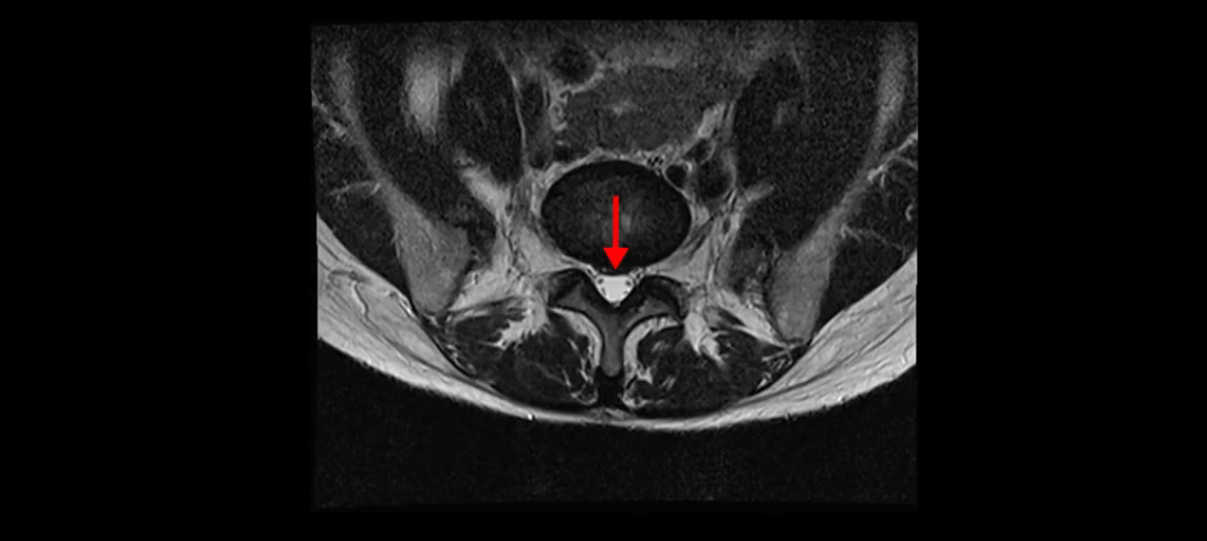

이분 MRI를 보시면 두 마디의 퇴행성디스크가 있습니다. 그리고 디스크가 조금씩 밀려 나와 있고요. 그런데 디스크 탈출 정도는 두 마디 다 심하지 않습니다. 4번 5번에는 디스크 탈출이 약간 있고,

5번 1번은 디스크 탈출이 가운데 쪽으로 살짝 있습니다.

중요한 것은 이 정도 경미한 탈출과 협착으로는 양쪽 다리가 저리고 아플 수가 없습니다.

이분 MRI를 보시면 퇴행성디스크가 있고 약간의 협착이 있지만 이 정도의 퇴행성디스크와 협착으로는 신경이 눌려서 양쪽 다리가 저리고 아픈 증상이 나올 수가 없습니다. 그래서 MRI와 이 환자분의 다리 증상이 매치가 안 된다고 하는 의사들이 많은 겁니다.